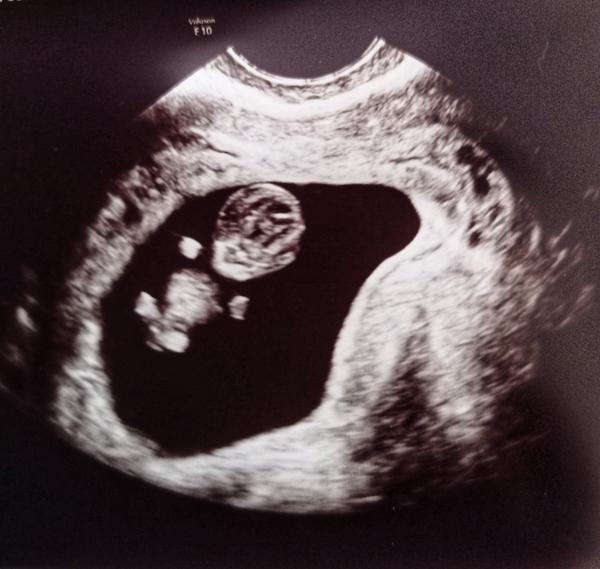

Baby nevzdávajte sa!! A každej z Vás by som chcela dopriať tento pocit. Som síce na začiatku (13 týždeň) preto som čakala než pominie to kritické obdobie, aby som sa svetu pochválila.